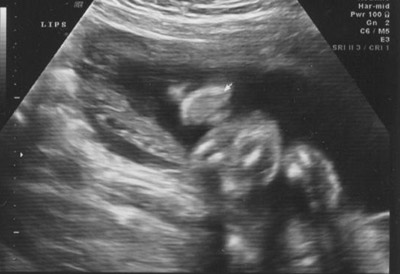

And lips looking staight at them, not as easy to see if you weren't there in person: